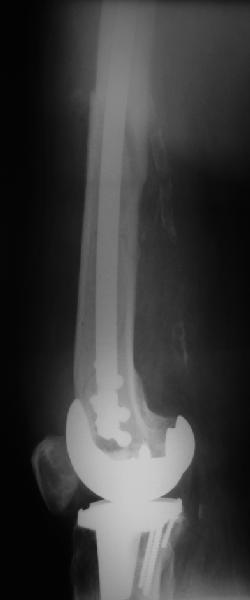

В приложении - недавний перипротезный перелом.

Методичка по закрытому интрамедулярному остеосинтезу при дистальных переломах бедра тут.